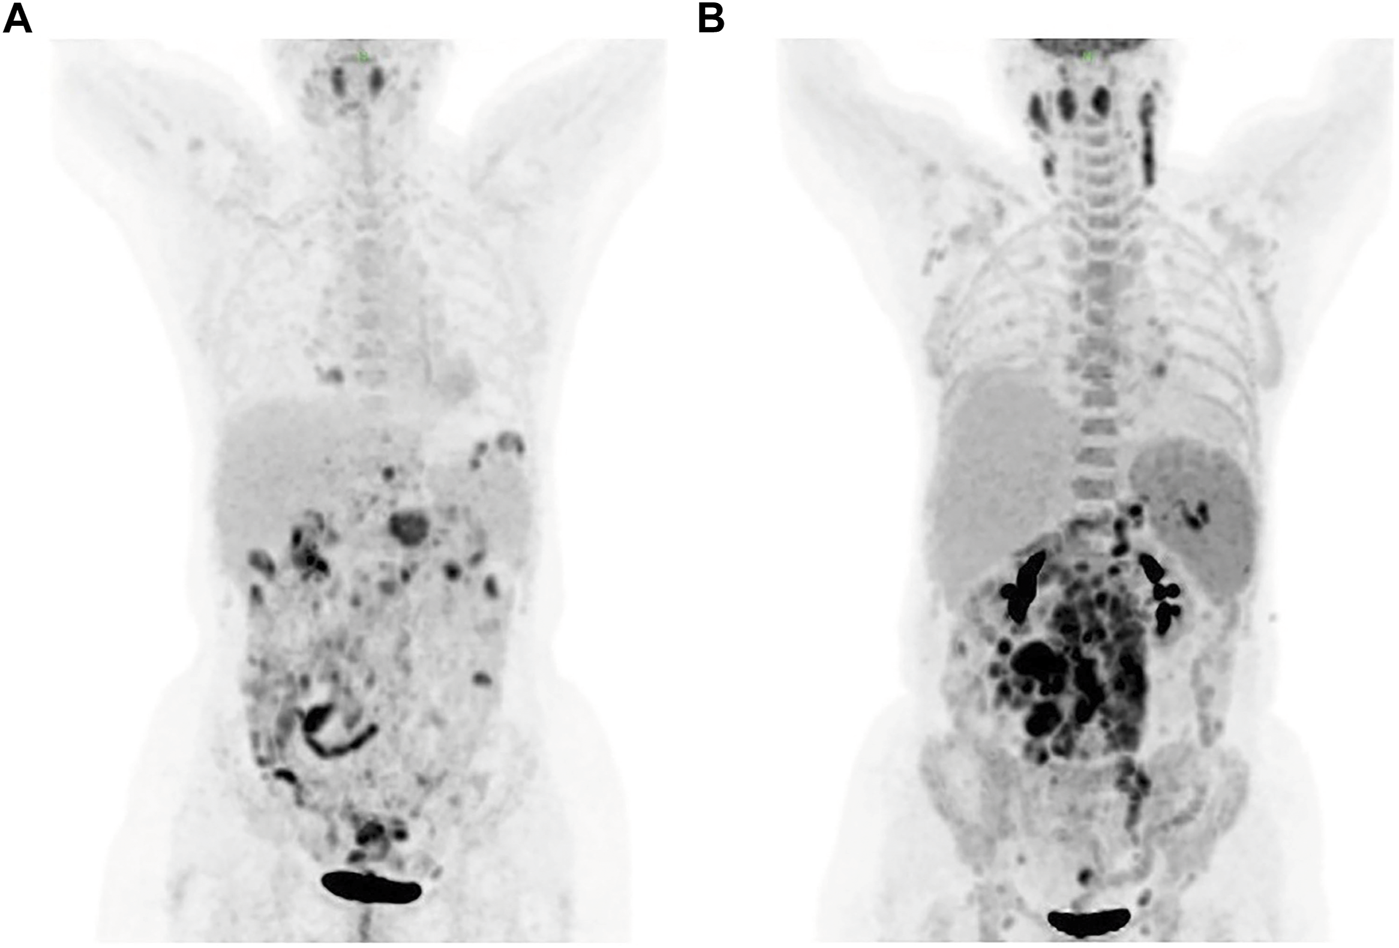

A 57-year-old female was presented to the hospital on 6 April 2020 with hypereosinophilia for 3 years and abdominal discomfort for 8 months. Physical examination showed that the upper abdomen was slightly tender on palpation. Laboratory data showed that the eosinophil count was 33.67×109/L. Lactate dehydrogenase (LDH) was slightly elevated (356 U/L). Serum total immunoglobulin E (IgE) was elevated (315.149 KIU/L). Hepatitis B virus (HBV) testing showed that HBsAg, anti-HBe, and anti-HBc were all positive, but no HBV-DNA was detected. EBV-DNA was also undetectable. Bone marrow (BM) examination showed significantly increased eosinophils (Figure 1). The immunoglobulin heavy chain (IGH) and the T-cell receptor (TCR) gene rearrangements were negative based on PCR analysis of the BM. Gene detection by NGS in BM indicated that JAK2 V617F, PDGFRα, PDGFRβ, and FGFR1 were all negative. Cytogenetics showed an abnormal karyotype with 45, XX, -13 (1); 45, XX, -16 (1); 46, XX (18) (Supplementary Figure S1). Then, positron-emission tomography with 18F-fluorodeoxyglucose (FDG-PET) was performed. As shown in Figure 2A, the FDG-PET on 9 April 2020 showed positive FDG uptake in multiple enlarged lymph nodes throughout the abdominal cavity and in the duodenum, terminal ileum, and colon. Two gastrointestinal specimens on 12 April 2020 and 3 May 2020 showed eosinophil invasion (Supplementary Figure S2). We also performed a laparoscopic lymphadenectomy on 17 April 2020, but it didn’t show any diagnostic significance. Ultimately, the diagnosis of idiopathic eosinophilia was made and imatinib combined with prednisone regimen was restarted.

FIGURE 2

FDG-PET showed positive FDG uptake in multiple enlarged lymph nodes on 9 April (A) and 30 July (B), respectively. FDG-PET, positron-emission tomography with 18F-fluorodeoxyglucose.